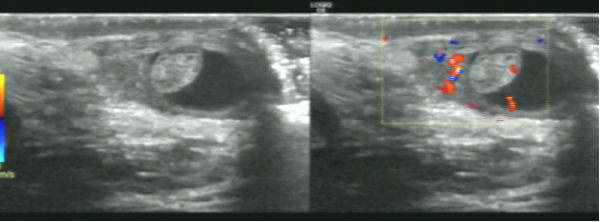

急性睾丸附件扭转,是小儿泌尿系统常见急症之一,常见于8-13岁的患儿,是引起小儿急性阴囊疼痛的主要因素,左侧较右侧发生率高,成年人极少见,症状酷似睾丸扭转,易与急性睾丸附睾炎和睾丸扭转相混淆,术前诊断率<20%。超声诊断是睾丸附件扭转首选检查。